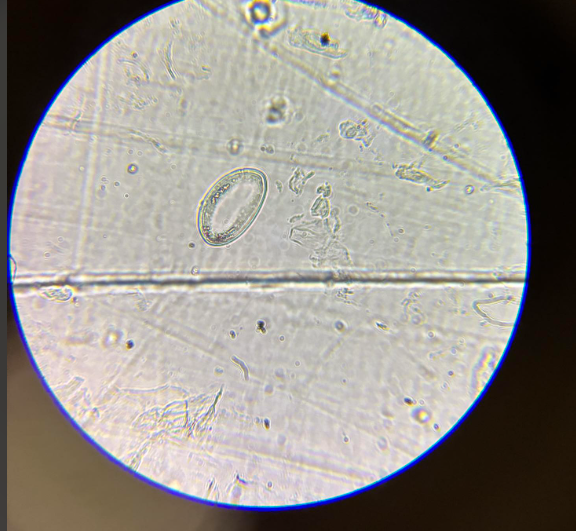

enterobius vermicularis jaja